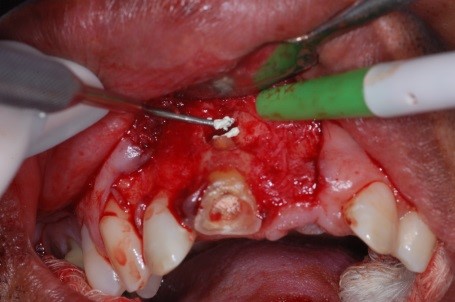

- Figura 15 – Colocação do material MTA.

- Figura 16 – Condensação do MTA no conduto.